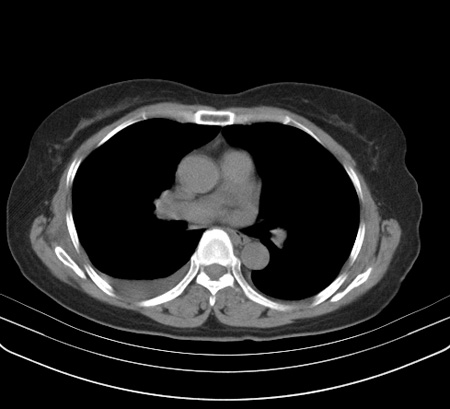

以下是引用余辉在2009-2-19 20:10:00的发言:[br]多考虑急性感染性病变,右中叶尚可见多枚小斑片状影,多为化脓性肺炎,双侧胸腔积液

以下是引用随光逐影在2009-2-19 20:33:00的发言:[br]1)考虑右肺炎症;建议抗炎治疗后复查。2)双侧胸腔积液(以右侧为甚)。

以下是引用花凤凰在2009-2-19 20:46:00的发言:[br]病人有发热,胸痛急性起病,主要病变位于右肺中叶外侧段,呈楔行改变,位于外带胸膜下,考虑为肺梗塞可能!!!!!!!!!!!!!!!!!!!!!!!!!!!!!!!!!!!